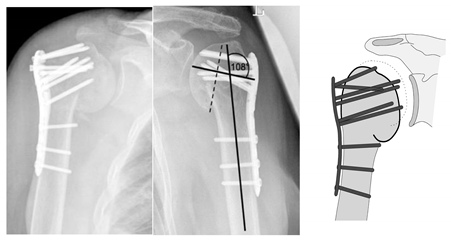

| Complication Type | Exemplary Images by X-rays or Pattern Images | Definition |

|---|---|---|

| 2a | ![]() | Complication Type 2a is defined by varus displacement (<20°) of the humeral head associated with screw cutout through the humeral head cortex. The head sintering is considered relatively stable and non-progressive. |